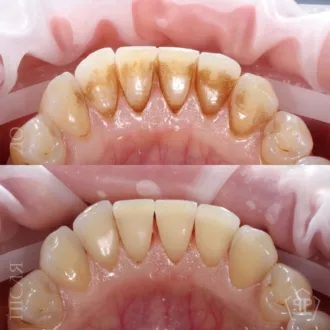

Комплексная гигиена зубов: гигиеническая чистка скейлером + аппаратом Air-Flow + полировка зубов профессиональной пастой